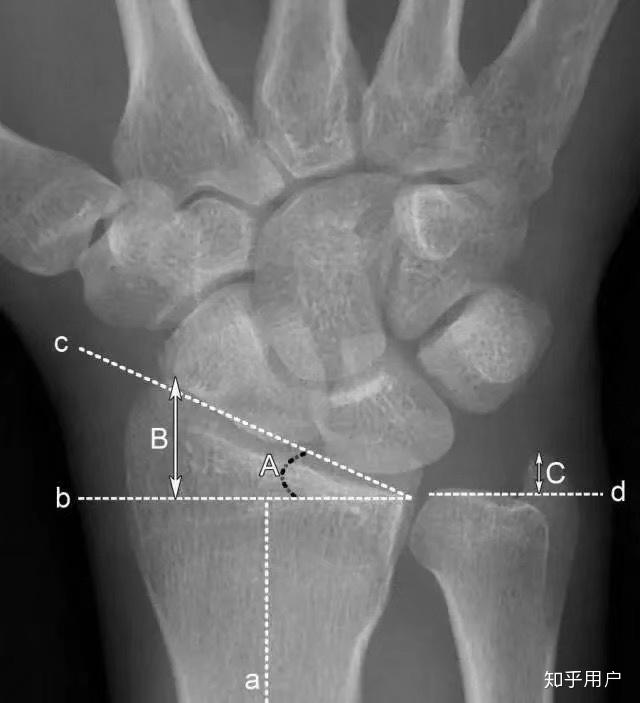

三角纤维软骨复合体(triangular fibrocartilage complex,tfcc)是指腕

tfcc全称triangular fibrocartilage complex,又称三角纤维软骨复合体